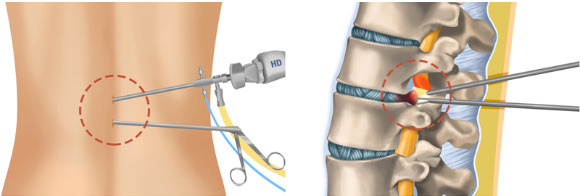

https://adsense.google.com/adsense/u/1/pub-9161951367286286/myads/sites/preview?url=notion6988.tistory.com 🦴 '뼈를 깎는 아픔' 없이 척추 수술 새 길 열었다